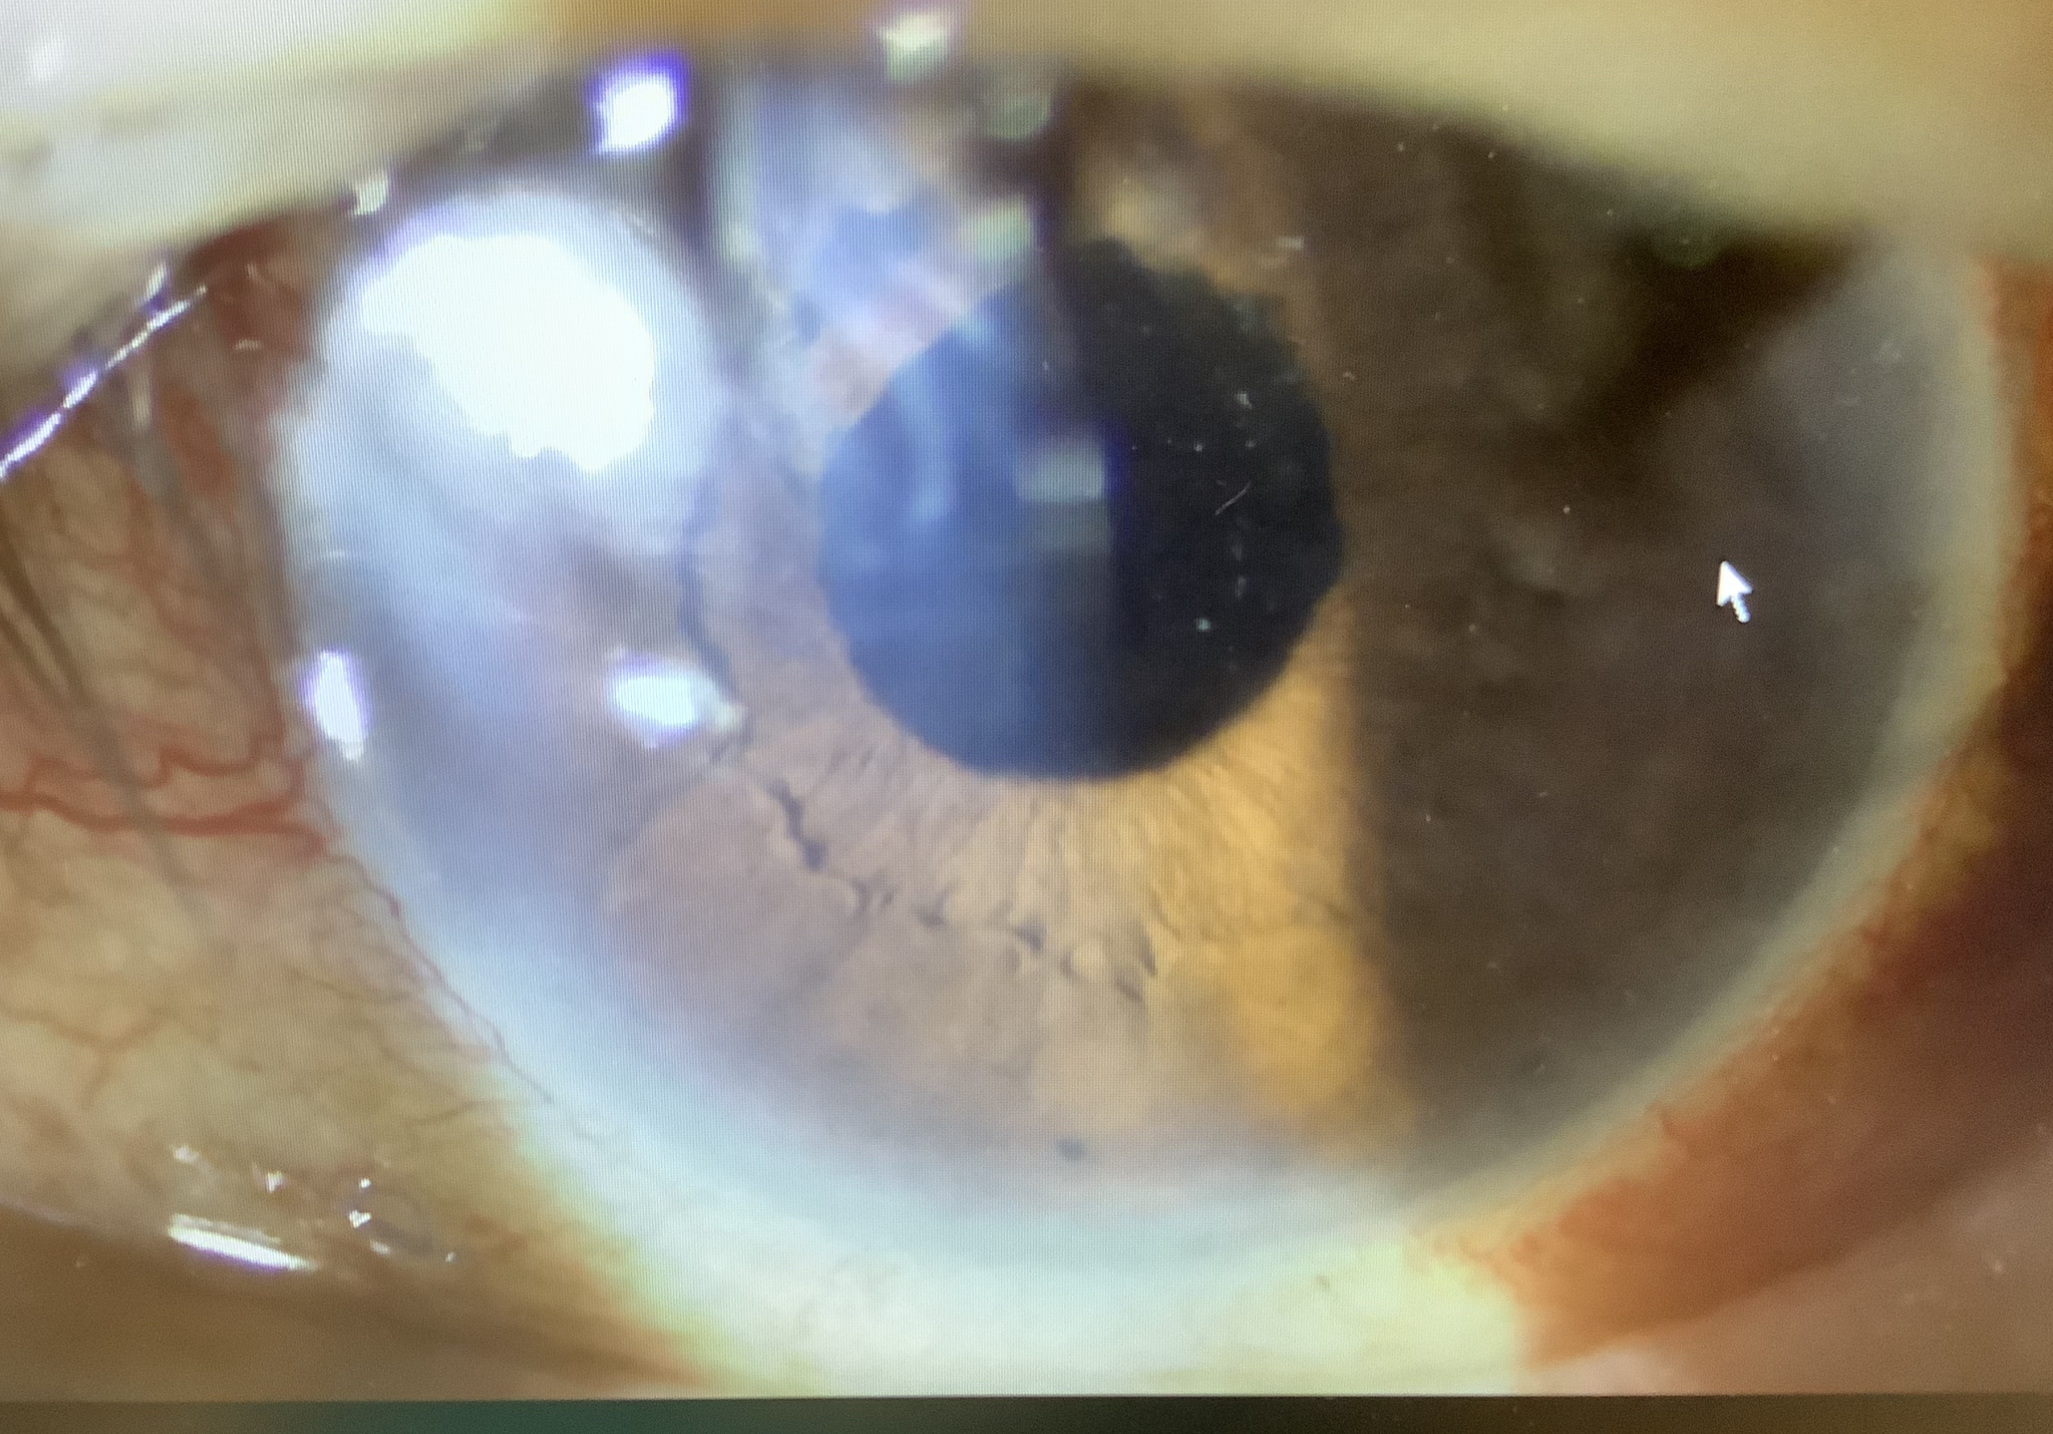

↑月曜日に硝子体手術をして炎症もだいぶ治まってきました。